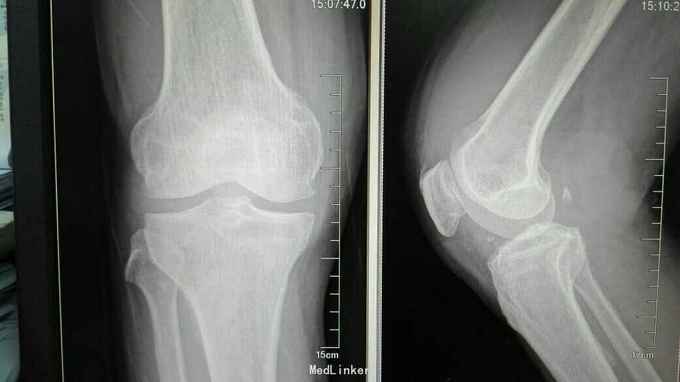

查体:右膝稍肿胀,皮温正常,右膝髌上囊处压痛(+),右膝屈曲稍受限(0~100度),余查体正常。 辅助检查:血常规、ESR、CRP正常 膝关节正侧位片:右膝关节退行性变,髌上囊肿胀 膝关节MRI提示:右膝髌上囊软组织占位,侵犯至股四头肌,考虑滑膜肉瘤可能性大 关节镜取活检提示滑膜肉瘤 全身PET-CT未见其它部位转移,肺无转移